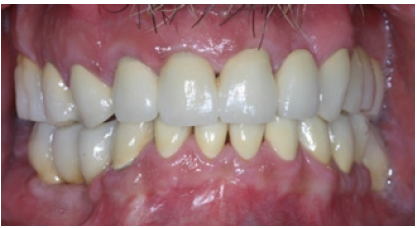

In order to optimize final aesthetics the 5 mandibular anteriors were prepared for all ceramic restorations. Four all ceramic veneers (E-max Ivoclar Co, Liechtenstein) and an all ceramic crown (#42) completed the final restorations. A final occlusal splint was also fabricated chairside (prior to the final cementation of ceramic veneers) for the protection of final restoration and control of TMJ function (Figure 19,20). Minimal occlusal modifications of the splint were necessary after final cementation of mandibular anteriors. The final radiographic examination was kept as a record for future re-examinations (Figure 21). Finally, the patient was enrolled to a 3 months recall program. In each recall and maintenance visit, the periodontal tissues, the abutments and the stomatognathic system were thoroughly examined, preventive regimens were applied and patient compliance was assessed. Two years later, the excellent periodontal condition and performance of the restoration was registrated (Figure 22-24). The patient complied with proper oral hygiene, reduced smoking and adopted a regular use of the occlusal splint. Strict recall and maintenance visits were necessary for long term success of this full mouth rehabilitation. The patient stopped smoking immediately after 6 months and changed nutritional habits in order to eliminate secondary caries.

Figure 20: Final restorations after cementation of the all ceramic veneers.

Figure 22: Final restorations in protusion.

Figure 23: Right side view of final restorations (one year recall).

Figure 24: Left side view of final restorations (one year recall).